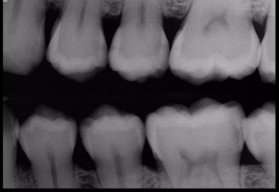

Radiographs